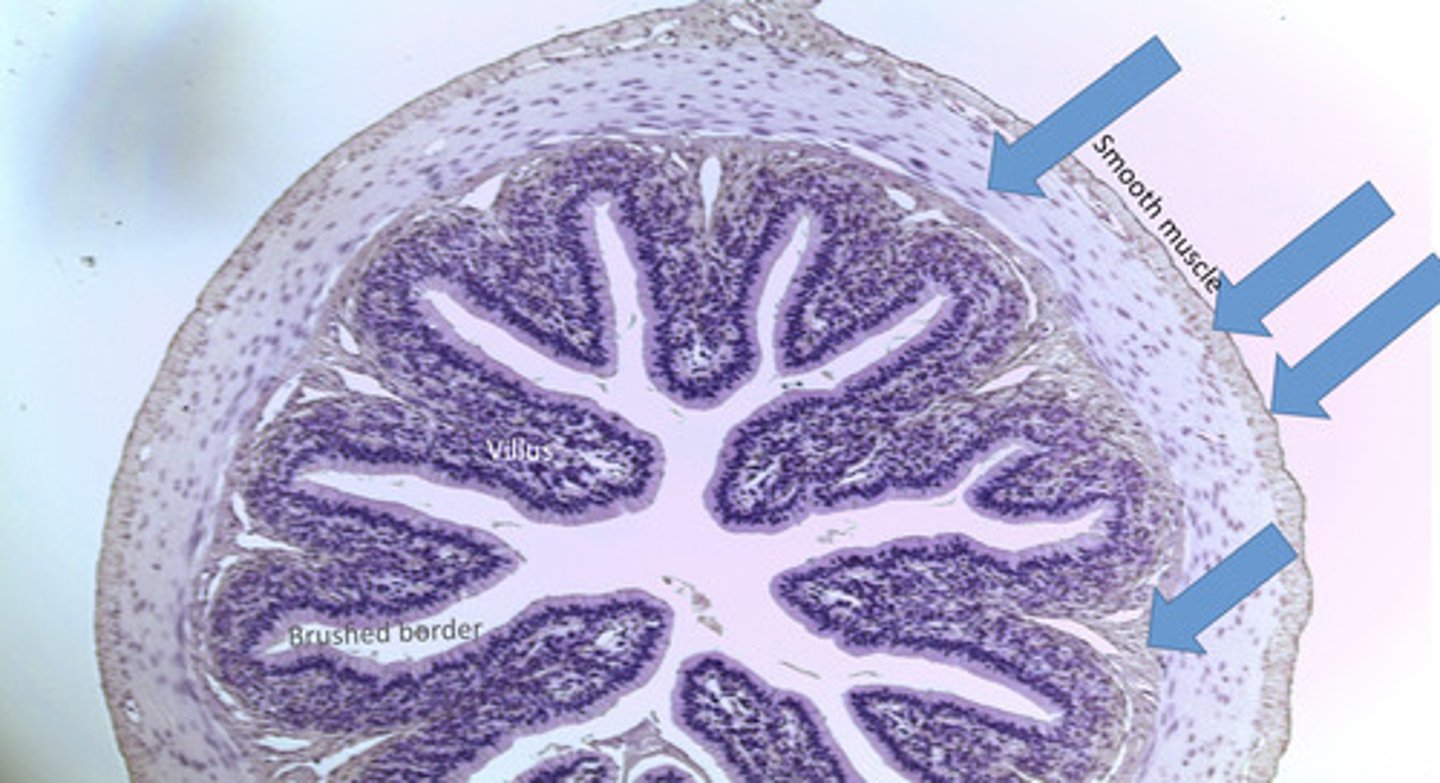

villi

Tiny finger-shaped structures that cover the inner surface of the small intestine and provide a large surface area through which digested food is absorbed

brush border

Surface of a cell covered with microvilli. increases surface area of a cell for absorption

smooth muscle

involuntary muscle found in internal organs

Small intestine